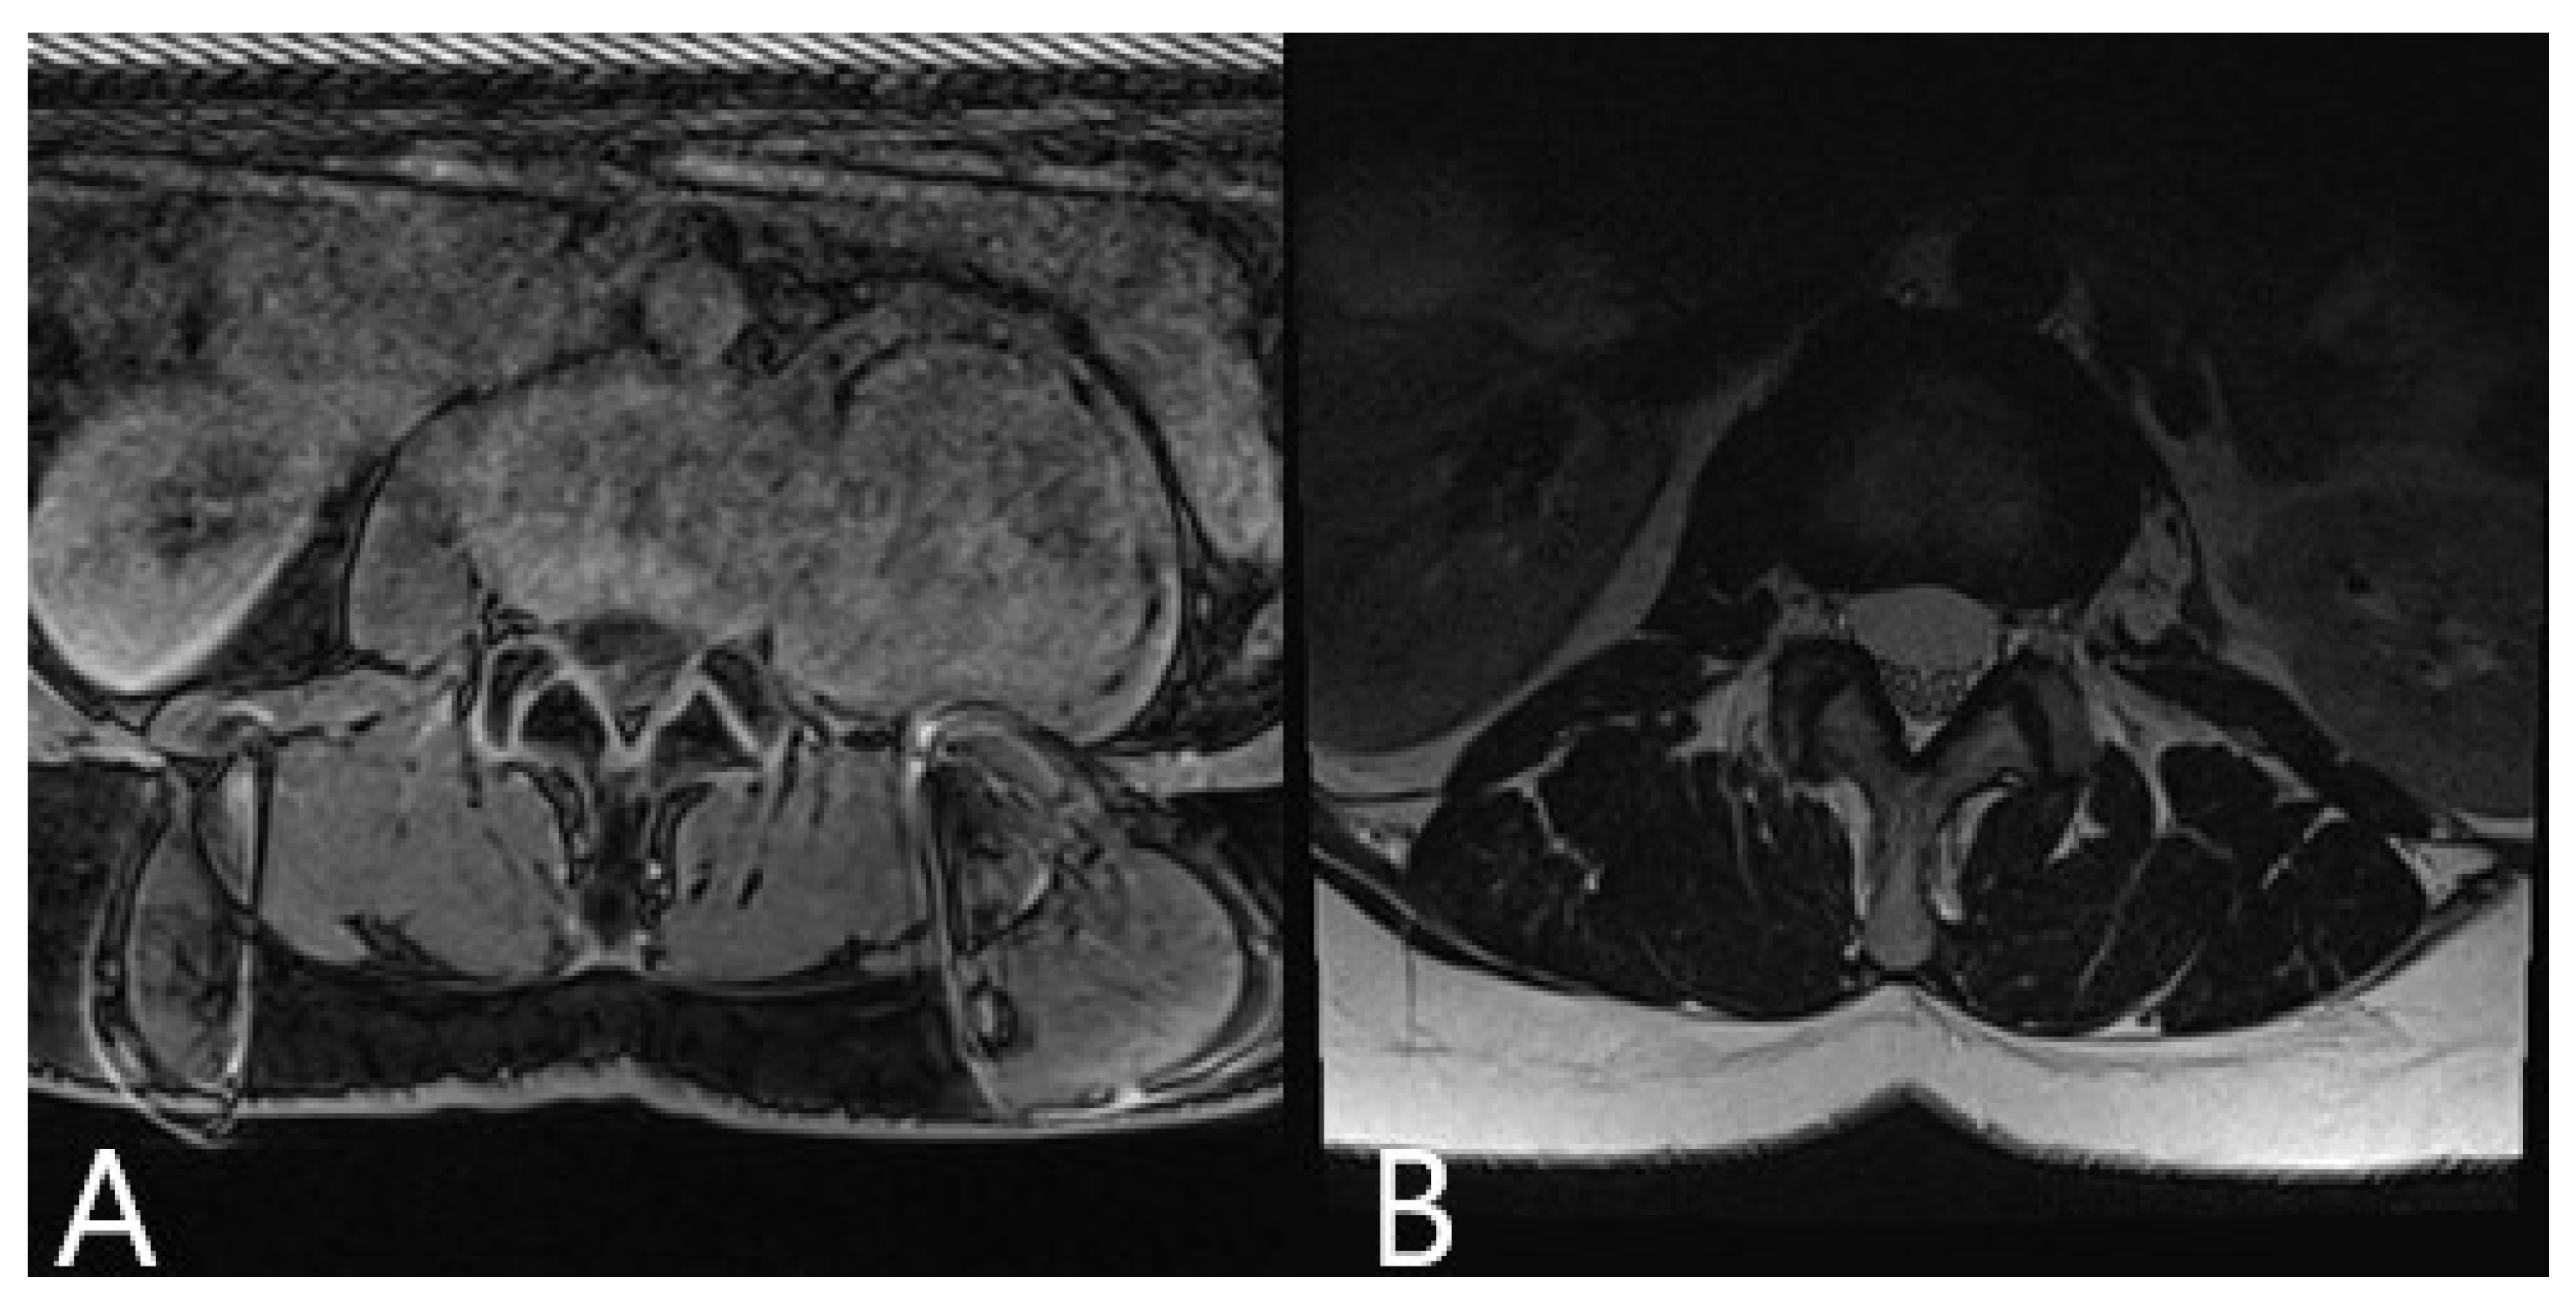

| 3 | 66 | F | Calcified herniated disc Th 9/10 | Ataxia Paraparesis 4/5 | Left lateral retropleural approach, sequestrectomy of the herniated disc | None | Improvement of ataxia following surgery |

| 4 | 19 | F | Giant aneurysmatic bone cyst Th 8/9 | Back pain | 1. Hemilaminectomy T8/9, Resection of the thoracic nerve origin 2. Tumor resection via left retropleural approach, Resection of 7/8 Rib with reconstruction of the thoracic wall | No | No pain, no deficits, and no recurrence at follow up |

| 8 | M | 51 | Herniated disc T8/9 with myelopathy | Back pain, paraparesis 3/5, urinary incontinence | 1. Partial resection of the herniated disc via posterior approach with right costotransversectomy 2. Resection of the remaining disc via left retropleural approach 3. Stabilization T8-9 | No | No pain and no deficits following surgery |

| 9 | F | 52 | L2 Neurinoma | Back and hip pain | Resection of neurinoma via left retroperitoneal approach | No | No pain, no deficits, and no tumor recurrence at follow up |

| 10 | F | 63 | Herniated disc T 7/8 with myelopathy | Worsening of back pain due to chronic pain syndrome following multiple spine surgeries, ataxia | Left lateral retropleural approach, sequestrectomy of the herniated disc | No | Chronic pain syndrome with moderate improvement, no ataxia, no deficits at follow up |

| 14 | F | 48 | Schwannoma Th11/12 | Back pain | 1. Resection of T12 nerve root via dorsal approach. 2. Left lateral transpleural approach, resection of the tumor | None | Improvement of back pain following surgery |

| 15 | F | 46 | Calcified herniated disc Th 7/8 | Back, pain, paraparesis | Left lateral retropleural approach, constotransversectomy, total resection of the herniated disc | None | Improvement of back pain and paraparesis following surgery |

| 16 | M | 38 | Calcified herniated disc Th 9/10 | Back pain, paraparesis | Left lateral retropleural approach, costotransversectomy, subtotal resection of the herniated disc | None | Improvement of back pain and paraparesis following surgery |